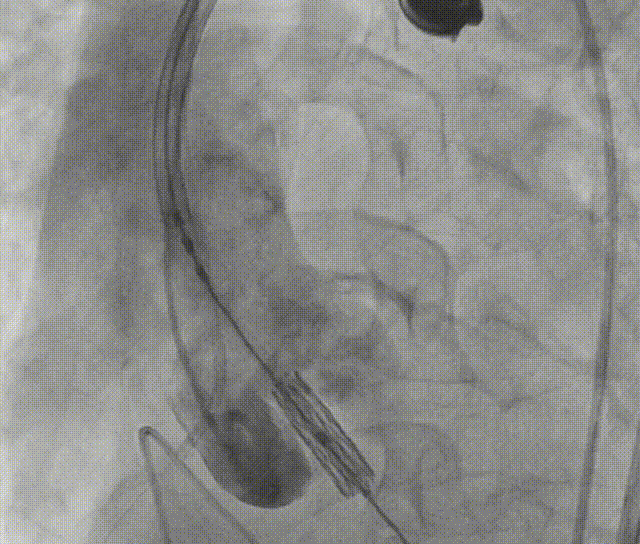

全麻下建立双侧股动脉入路,以右股动脉为主;导丝跨瓣后置换猪尾导管,确定共平面。

图片